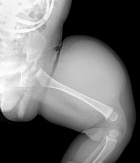

E.J.- five month old boy, presents with left thigh mass noticed within the first month of life.

The mass seems not to bother him. He is reaching all milestones.

Zoom image: Radiological image Radiological image.